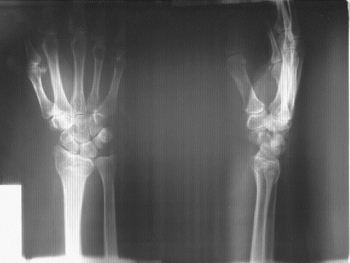

На запорожском облэнерго произошел несчастный случай. Женщина сломала лучевую кость.

По его информации, 45-летняя экономист предприятия упала с высоты своего роста. На место была вызвана бригада медиков. У женщины оказался перелом лучевой кости.